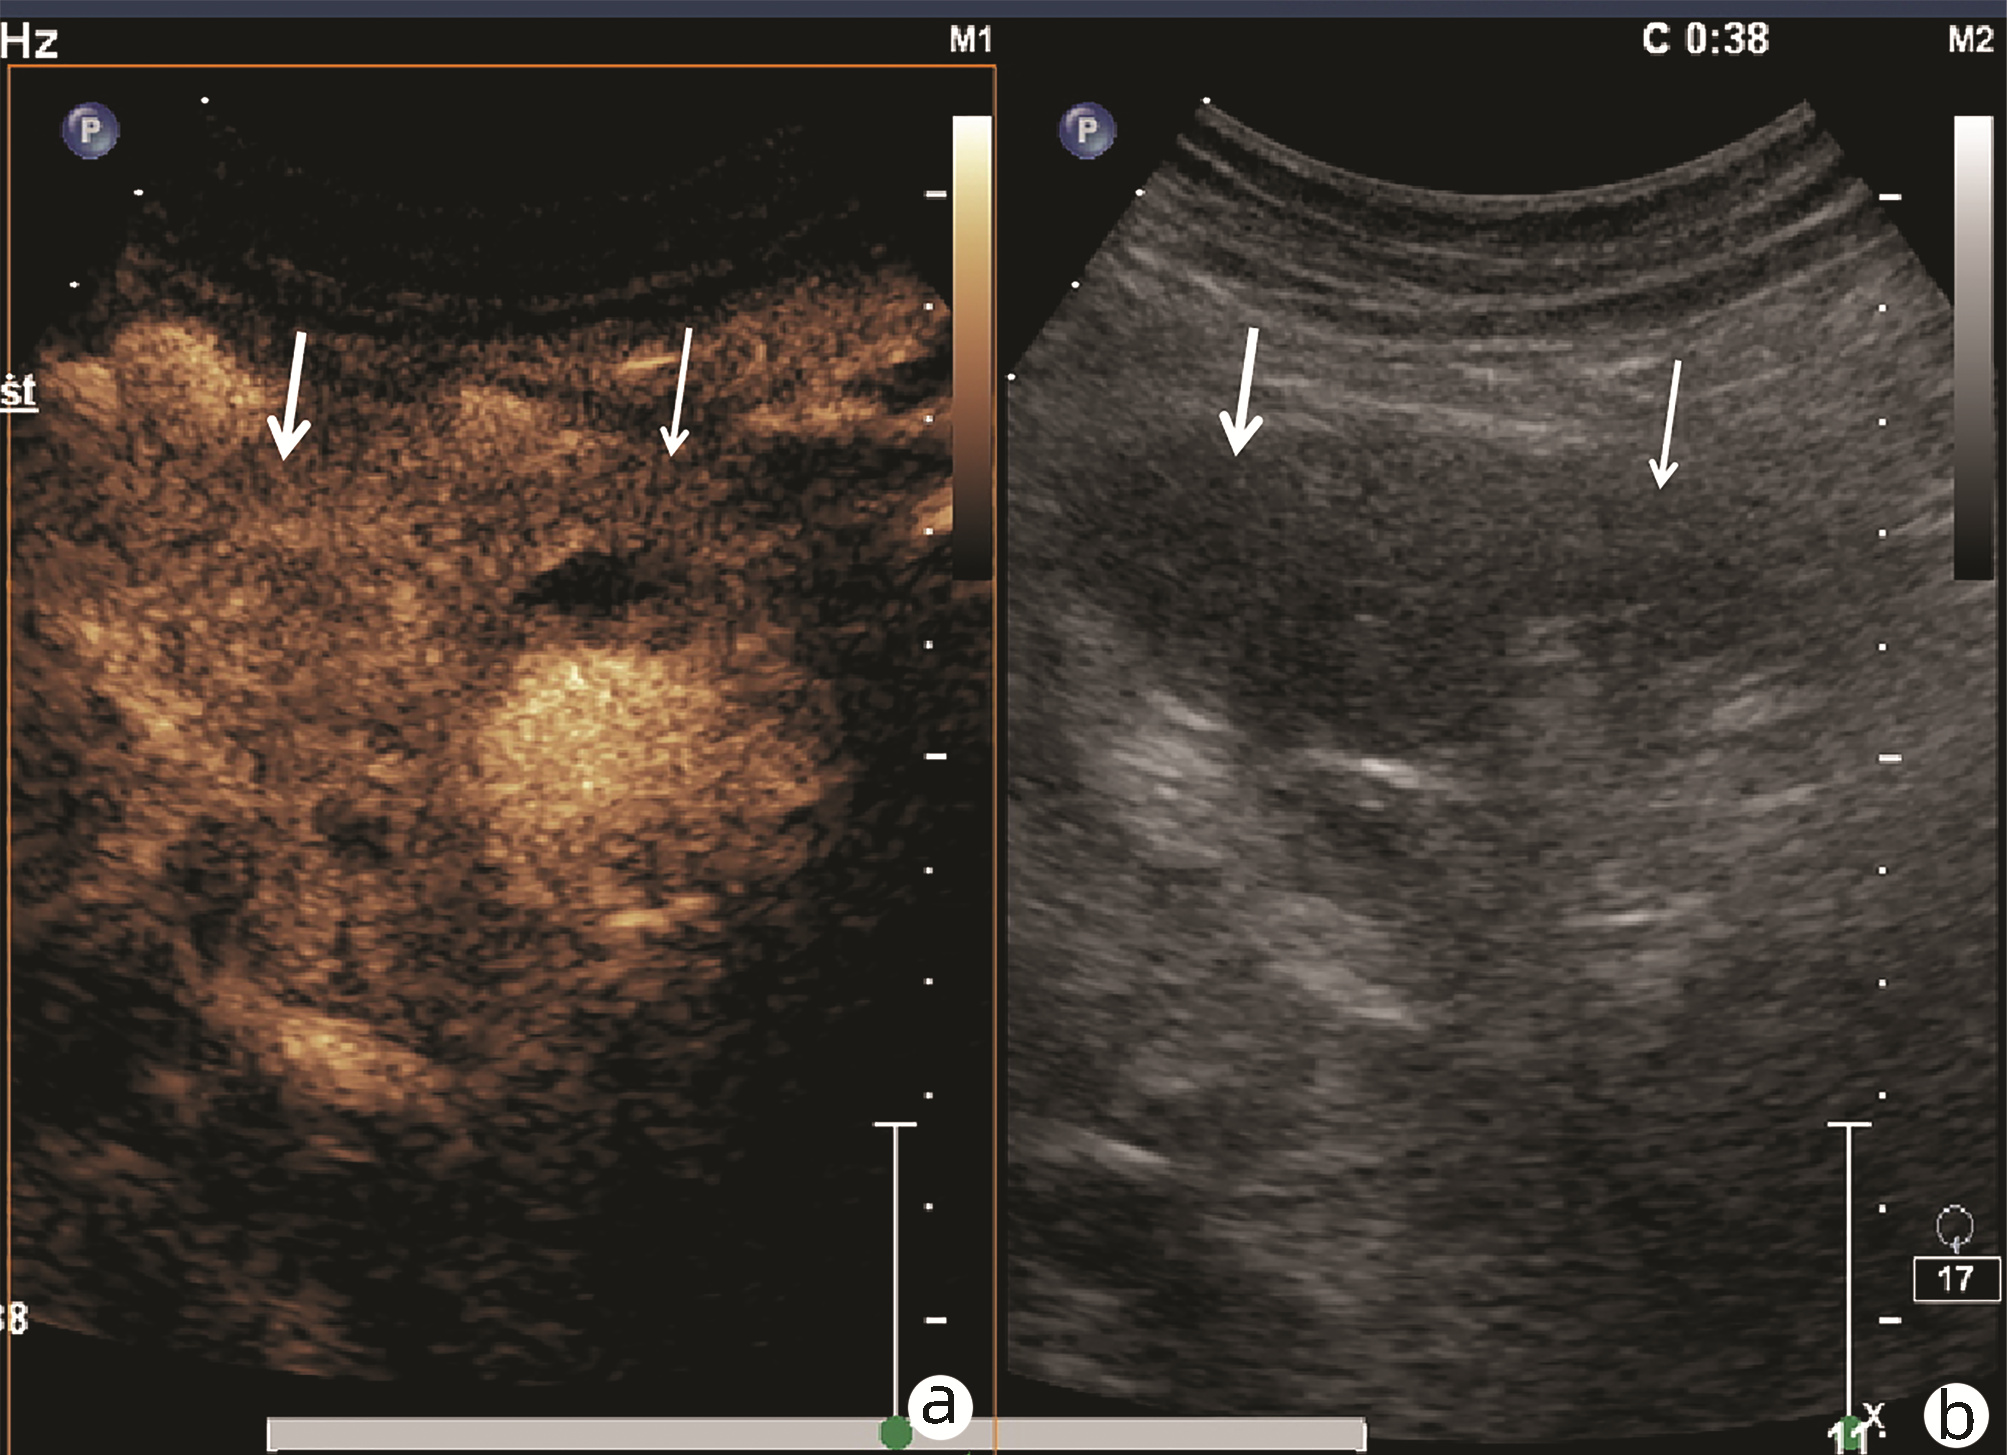

Ultrasound findings and contrast-enhanced ultrasound findings of mass-type autoimmune pancreatitis versus pancreatic ductal adenocarcinoma

Xiangliu OUYANG, Yunxia HAN, Lichun ZHENG, Yingchun ZHAO, Xinyu SHEN, Wenjun ZHANG, Yanbin WANG

2022, 38(6): 1351-1355. DOI: 10.3969/j.issn.1001-5256.2022.06.025

Abstract(1427) HTML (553) PDF (3738KB)(50)

Abstract:

Objective  To investigate the value of ultrasound and contrast-enhanced ultrasound (CEUS) in the differential diagnosis of mass-type autoimmune pancreatitis (AIP) and pancreatic ductal adenocarcinoma (PDAC).  Methods  A retrospective analysis was performed for the clinical data, ultrasound findings, and CEUS findings of 11 patients with mass-type AIP who were diagnosed in Tangshan Workers' Hospital from January 2015 to December 2020, and their characteristic manifestations were analyzed and compared with the data of 23 patients with PDCA. The chi-square test was used for comparison of categorical data between two groups.  Results  For the 11 patients with mass-type AIP, CEUS had a diagnostic accuracy of 63.64%, and all of these patients had hypoechoic single lesions; the patients with clear boundaries, regular morphology, pancreatic duct dilatation or cutoff, and blood flow signal accounted for 54.55%, 63.64%, 18.18%, and 36.36%, respectively, while in the PDCA group, such patients accounted for 30.43%, 34.78%, 78.26%, and 21.74%, respectively, and there was a significant difference in the presence or absence of pancreatic duct dilatation or cutoff between the two groups(χ2=11.089, P < 0.05), with no significant differences in the other indices (all P > 0.05). For the 11 patients with mass-type AIP, CEUS showed that 7 patients (63.64%) had hyperenhancement and 4 (36.36%) had iso-enhancement in the arterial phase, and 5 patients (45.45%) had hyperenhancement in the arterial phase and 6 (54.55%) had iso-enhancement in the venous phase; for the 23 patients with PDCA, 22 (95.65%) had hypoenhancement of lesions in both arterial and venous phases, and there were significant differences in the enhancement pattern in arterial and venous phases between the two groups (χ2=30.345 and 30.084, both P < 0.05).  Conclusion  The enhancement pattern of CEUS and the presence or absence of pancreatic duct dilatation or cutoff have a relatively high value in the differential diagnosis of mass-type AIP and PDCA.